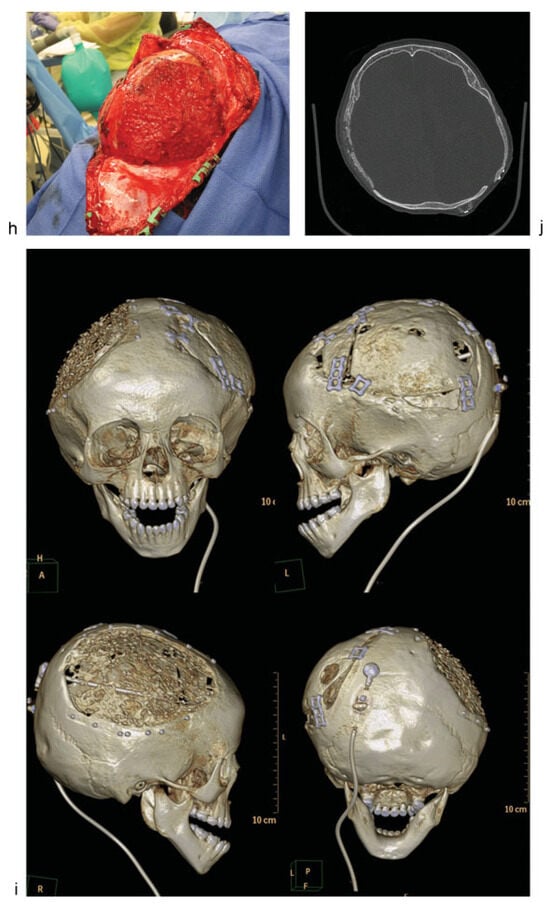

Case 1: An 18-month-old child with history of decompressive craniectomy for acute traumatic subdural hematoma, with at right frontal ventriculoperitoneal shunt in place for posttraumatic hydrocephalus. The autologous bone flap was retrieved from bone freezer storage and replaced 3 months after the initial trauma to repair the large left frontoparietotemporal skull defect. The autologous cranioplasty failed with bone flap resorption noted 6 weeks later, which was near complete by 4 months after autologous cranioplasty. An exchange cranioplasty was done, with re-siting of the ventriculoperitoneal shunt to the left occipital approach to avoid the bilateral cranioplasty areas. (a) Axial head computed tomographic (CT) scan immediately after autologous cranioplasty (left); axial CT scan of the same patient with bone flap resorption 4 months later (right). (b) Three-dimensional (3D) CT reconstructions showing bone flap resorption and right frontal ventriculoperitoneal shunt in place. (c) Axial CT scan (left) with corresponding intraoperative skull defect (right) at time of second reconstruction (exchange cranioplasty) after bone flap resorption. (d) Exchange cranioplasty. Measuring the donor site for the exchange and templating the cranial defect. (e) Exchange cranioplasty in process after placement of the freshly harvested contralateral bone graft. (f) Harvesting autologous particulates for bone grafting from the inner surface of a full-thickness calvarial flap. (g) Bilaminate mesh cranioplasty: inner layer of mesh in the right frontoparietotemporal calvarial defect, forming the epidural inner cortex. (h) Exchange cranioplasty completed with the recreated “diploic space” in between mesh layers filled autologous particulate bone mixed with demineralized bone matrix and autologous blood, then covered with the outer layer of mesh. (i) 3D CT scan 3 months after exchange cranioplasty showing partial consolidation of particulate graft on the left, incorporation of the full-thickness calvarial graft on the right with good skull contour. The shunt was re-sited to avoid the cranioplasty areas. (j) Axial CTscan 3 months after exchange cranioplasty.

When bone is needed to provide cranial coverage, there are several options if the removed bone is no longer available because of trauma, loss, or infection. These options from the cranium include full-thickness grafts, split-thickness grafts, and particulate bone grafts. These three reconstructive approaches all involve using bone from the healthy parts of the skull to repair the defect and have been shown to have a lower rate of resorption than grafts from elsewhere on the body.[22] Full-thickness calvarial grafts are often used when there is concern about healing, such as, in the cases of the previous failed reconstruction. This approach provides good coverage of the cranial defect but creates a donor site to be repaired. This type of defect can be done using an exchange cranioplasty (Figure 1d, e), in which the existing defect is repaired with the full-thickness calvarial graft, and the donor site is repaired with particulate bone graft harvested from the full-thickness graft. Rogers et al reviewed 20 cases, and found that 15 of 20 had complete healing, and the size of the defects decreased by an average of 96%. This exchange cranioplasty method, although it involves an additional operative site, has been found to be highly effective even for large cranial defects as children have high-osteogenic potential.[23]

Particulate grafts can also be used to repair defects directly. In young children, the supply of autologous bone is limited; particulate grafts can be advantageous as they can be harvested with minimal morbidity (Figure 1f).[24]

Bilaminate constructs with particulate grafts can be made by placing bioresorbable mesh endocranially on the dura, laying in bone particulates mixed with blood, demineralized bone matrix paste and other bone growth enhancing agents, and buttressing with an outer layer of bioresorbable mesh. (Figure 1g, h) This method has been used successfully to augment small and large defects. Chao et al report that all the 11 patients in their initial experience achieved clinically stable reconstructions.[25] This method has the benefit that the donor site returns to full thickness over time. It is best used when the reconstructive site has good healing potential and unscarred dura. Alternatively, an exchange cranioplasty or other reconstructive method may be indicated.[23,26] (Figure 1i, j).